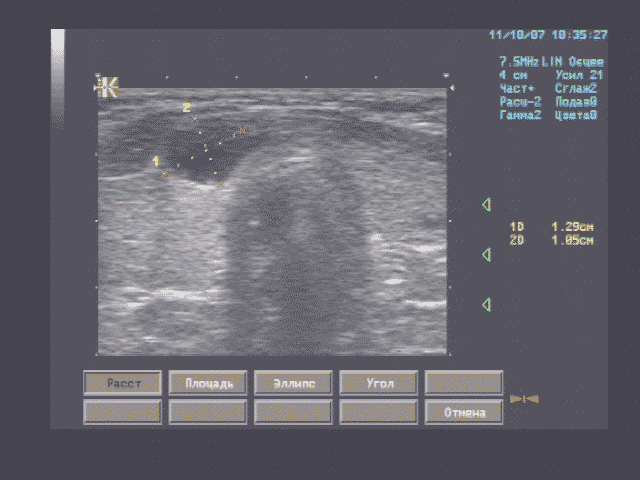

Печень - границы печени не расширены: нижний край правой доли у рёберной дуги, незначительно закруглён, переднезадний размер правой доли 119 мм, косой вертикальный 148 мм, переднезадний размер левой доли 59 мм, вертикальный 93 мм; контуры ровные, диафрагмальный контур нечёткий, паренхима неоднородная за счет гипоэхогенного участка вблизи правой боковой стенки желчного пузыря, имеющего округлую форму, диаметром 15 мм, имеющего ровные, относительно четкие контуры, однородное внутреннее строение; на остальном протяжении паренхима однородная, эхоструктура диффузно повышенной эхогенности рисунок зернистости нечёткий; внутрипечёночные жёлчные протоки не расширены, свободны, сосудистый рисунок обеднен.

Эхографические признаки хронического гепатита, гипоэхогенного очага 5 сегмента печени.